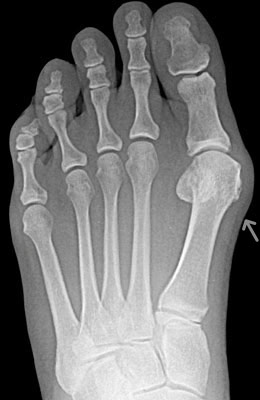

Before

Lapidus Forever Bunionectomy™ with Weil Procedure before

After

Lapidus Forever Bunionectomy™ with Weil Procedure

In this combined procedure, the joint behind the great toe joint, the 1st metatarsophalangeal joint, is fused together with the bunion in a more corrected position. Notice the improved alignment of the great toe joint. 2 screws were used to fixate the bones together and facilitate it towards fusion. In the Weil procedure, the 2nd metatarsal is shortened using a bone cut and fixed with a screw. Often, patients with a long 2nd metatarsal and a bunion will have pain underneath the ball of the foot. This procedure, in conjunction of correcting the bunion, helps to alleviate this pain.